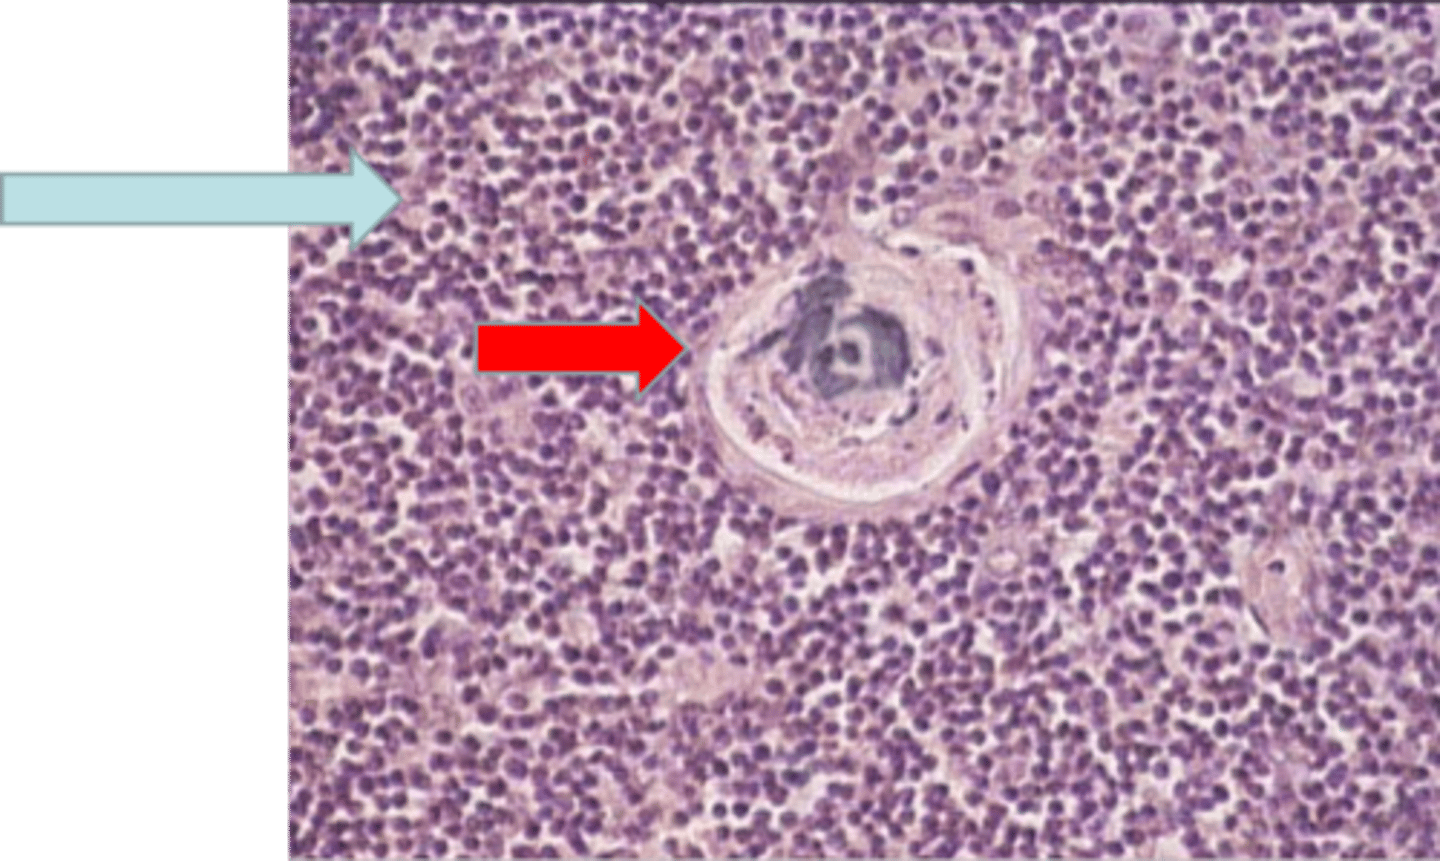

thymus

where is this tissue? thymus

medulla containing T lymphocytes

blue arrow medulla containing T lymphocytes

Hassall's corpuscle

red arrow Hassall's corpuscle

T lymphocytes

Identify the organ and major types of the cells found in this organ?

A) Hassall's corpuscle in the thymus gland

Identify the structure at the arrow?